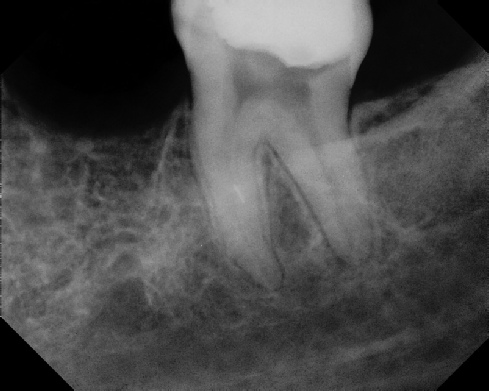

Pre-op Post-op 1 Post-op 2